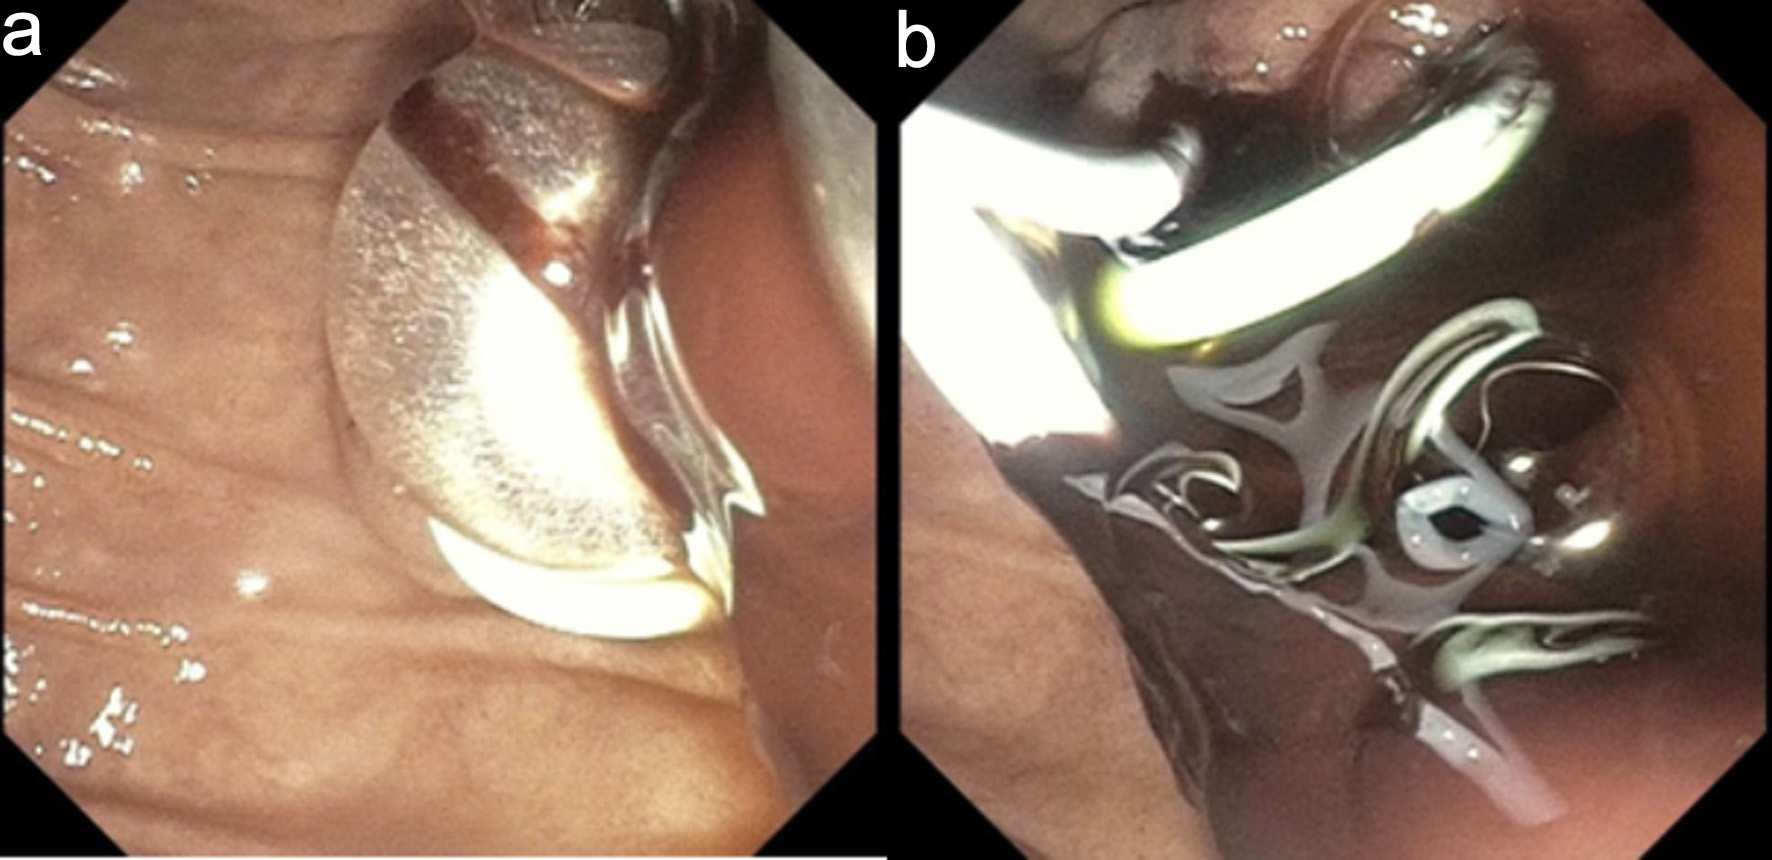

An emergent ERCP was performed. The major papilla appeared small, and the pancreatic duct was normal. The cholangiogram demonstrated a dilated biliary tree with multiple filling defects (Fig. 3a, b). A biliary sphincterotomy was performed, and the bile ducts were swept, yielding blood clots that were subsequently removed. A prophylactic pancreatic duct stent was placed to prevent post-ERCP pancreatitis. A temporary plastic stent was placed in the common bile duct to facilitate drainage (Fig. 4a, b).

Figure 4. Endoscopic retrograde cholangiopancreatography. (a) Endoscopic sphincterotomy followed by balloon sweep and extraction of blood clots. (b) Plastic bile duct and pancreatic duct stents were deployed to maintain biliary drainage and to prevent post-ERCP pancreatitis, respectively.